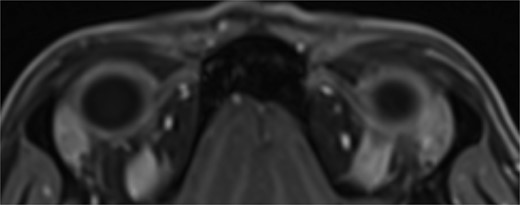

One month from initial presentation, the patient’s motility deficit progressed to bilateral moderate (−2) elevation deficit in adduction. A repeat MRI orbits yielded normal findings: there was no hypertrophy of the SO, no inflammation/hypertrophy of extraocular muscles, and no trochlear attachment (Fig. 3). Rheumatology input was sought regarding the possibility of acquired Brown syndrome; however, serology for mixed connective tissue disease, SLE, and rheumatoid arthritis was negative. The patient was treated for a total of 11 months on oral prednisolone at a maximum of 50 mg daily, which was slowly tapered and replaced with steroid-sparing, immune-modulating agents methotrexate and hydroxychloroquine.

T1 axial image of orbits which shows a normal trochlear-tendon complex.